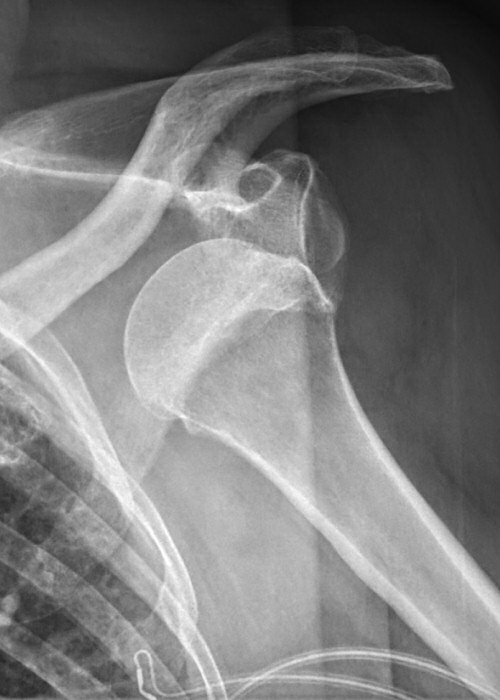

Främre luxation

Efter reponering